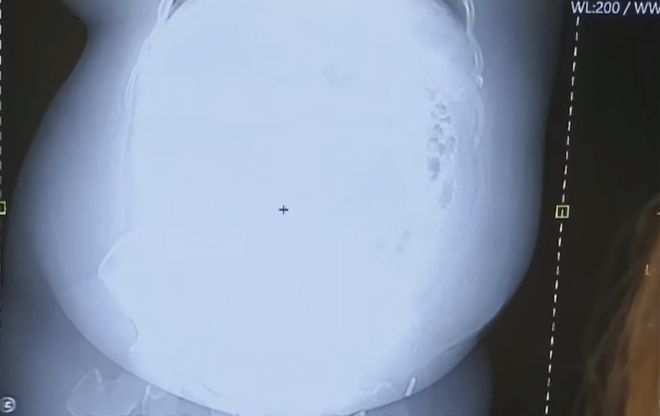

放射线在大胃袋面前也略显乏力,无法穿透脂肪下面的内脏,X光片显示的结果是一团白雾,再资深的医生看了良子的X光片都要冒几滴冷汗,网友建议“不如直接换成伽马射线吧”。

更戏剧性的是,车祸之后的良子去医院拍片子,被医生当场退货:良子的胃袋太大了,根本进不去核磁共振仪。视频画面可见,良子的胃袋上壁与核磁共振仪严丝合缝,堪称零公差工艺品。